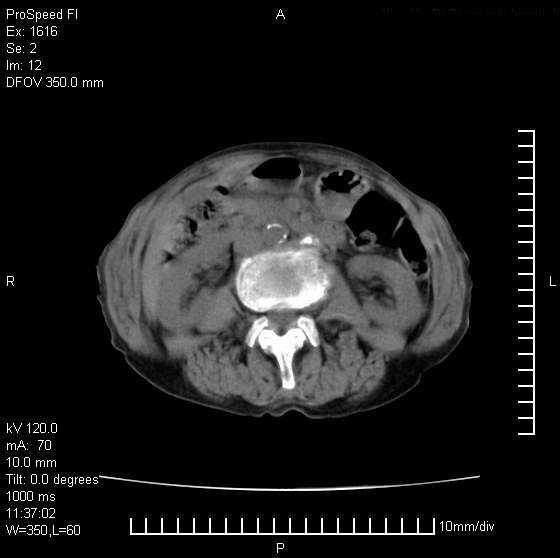

患者无明显临床症状,肝左叶发现一个圆形密度不均的低密度灶,边界较清楚,大小37x45mm,ct值35-70,患者犹豫做增强,如有增强片,我再发上,现先请各位老师会诊.

左肝外叶可见较大圆形低密度影,病灶可见较光整清晰边界,病灶内可见多量条状稍高密度影,右肝前叶亦可见圆形结节状低密度影,边界清晰,密度均匀,考虑1肝多发囊肿,左肝囊肿内出血2肝包虫病3左巨块型肝癌出血合并右肝转移或合并右肝囊肿

肝左叶类圆形低密度影,内可见略高密度影,边界清晰周边可见环形低密度带,考虑肝腺瘤可能,建议增强扫描除外肝血管瘤与肝癌

肝左叶类圆形低密度影,内可见略高密度影,边界清晰周边可见环形低密度带,考虑肝血管瘤

可能,建议增强扫描

肝左叶不均匀占位,内有斑片状高密度出血灶,内侧缘似有假包膜,腹主动脉周围及肝门区结构紊乱,似有增大淋巴结,考虑:肝左叶hcc并淋巴结转移。建议增强扫描除外其他。